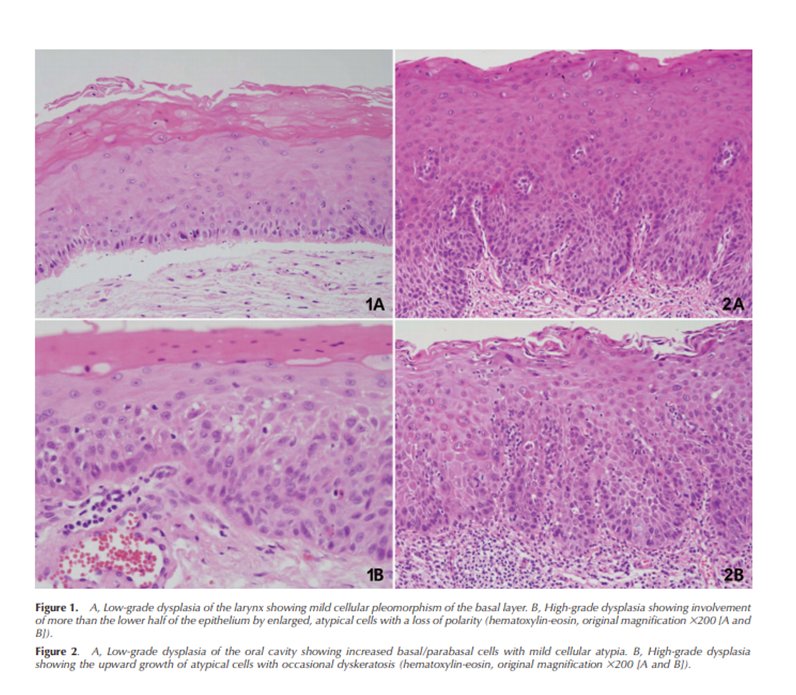

Recent changes to WHO classification of squamous intra-epithelial lesions of the head and neck discussed in this month's Arch Pathol Lab Med buff.ly/2KKKkAR